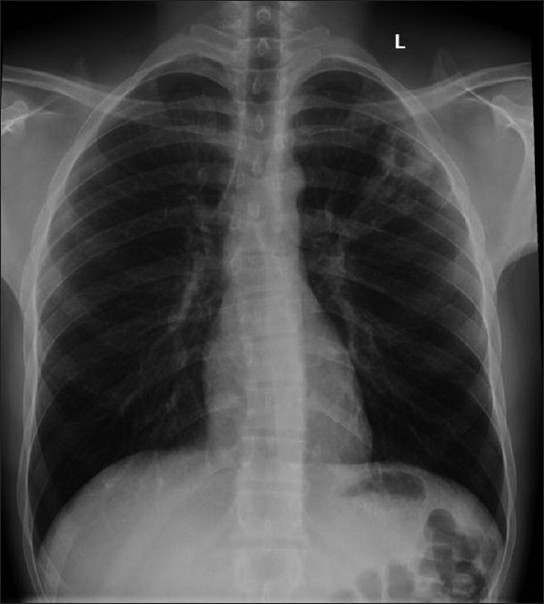

However, the immunocompetent individuals; are least infected with this microorganism. In rare cases; where immunocompetent individuals are infected, they show no symptoms at all. In individuals with a well-developed immune system, radiographic features, clinical presentations, and laboratory investigations are non-specific. Due to the non-specific or asymptomatic nature, it is sometimes confused with other diseases like lung cancer.

As mentioned above, in the case of immunocompetent patients, symptoms are not visible at all, and for this reason, the infection is confused with other diseases.